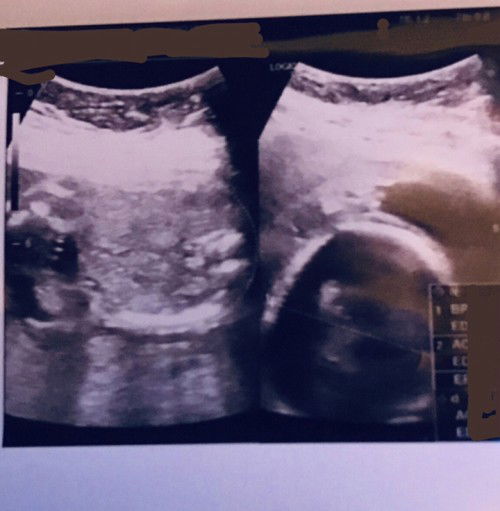

Hallo bun mau curhat donk, jadi ceritanya kemarin saya habis usg di klinik alhamdulillah normal semua tapi yang buat saya sedih adalah dokternya satset banget saat usg nya bahkan 5 menit aja gak ada, padahal saya pengen banget liat posisi bayi saya gimana di usia 22week ini tapi hasilnya gak jelas begini bahkan suami videoin aja gak sampe 2 menit selama itu gak ada posisi bayi lagi ngapainnya posisi kaki dimana & tangan dimana aja gak dijelasin 🥲 saat pemeriksaan dokternya gerak2in alatnya gak jelas & cepet2 gitu gak pelan untuk penjelasannya emang lugas terkesan buru2 sih intinya normal gitu. Btw saya nanya2 kok cuman ya itu penjelasan dokternya cepet banget cara ngomongnya, jujur sekecewa itu sampe saya gak bisa tidur plus sedih juga karna pengen liat dede yg jelas gitu dibanding saat usg usia 14week malah lebih jelas itu detail banget posisinya sedang apa & gimana bentuknya, sebelumnya saya periksa di klinik yg sama juga hnya beda dokter karna dokter sebelumnya kurang enak juga. Menurut bunda2 saya berlebihan gak karna kecewa hasil usgnya begitu? Mungkin bunda2 punya rekomendasi klinik/dokter kandungan di daerah bandung timur? #ingintahu #firstmom #pleasehelp

Hallo bun duh saya gabisa tidur nih karna gak sabar mau liat dede besok mohon doanya ya semoga dede sehat selalu sampe persalinan nanti 😁🤲 berhubung usia kandungan saya sudah menginjak 23 week boleh saran untuk nanya apa aja ke dokternya? Sebenernya dokter nya interaktif sih ngasih tau ini itu tanpa ditanya tapi kadang namanya kita awam jadi merasa kurang detail aja hehe #ingintahu #firstmom #pleasehelp